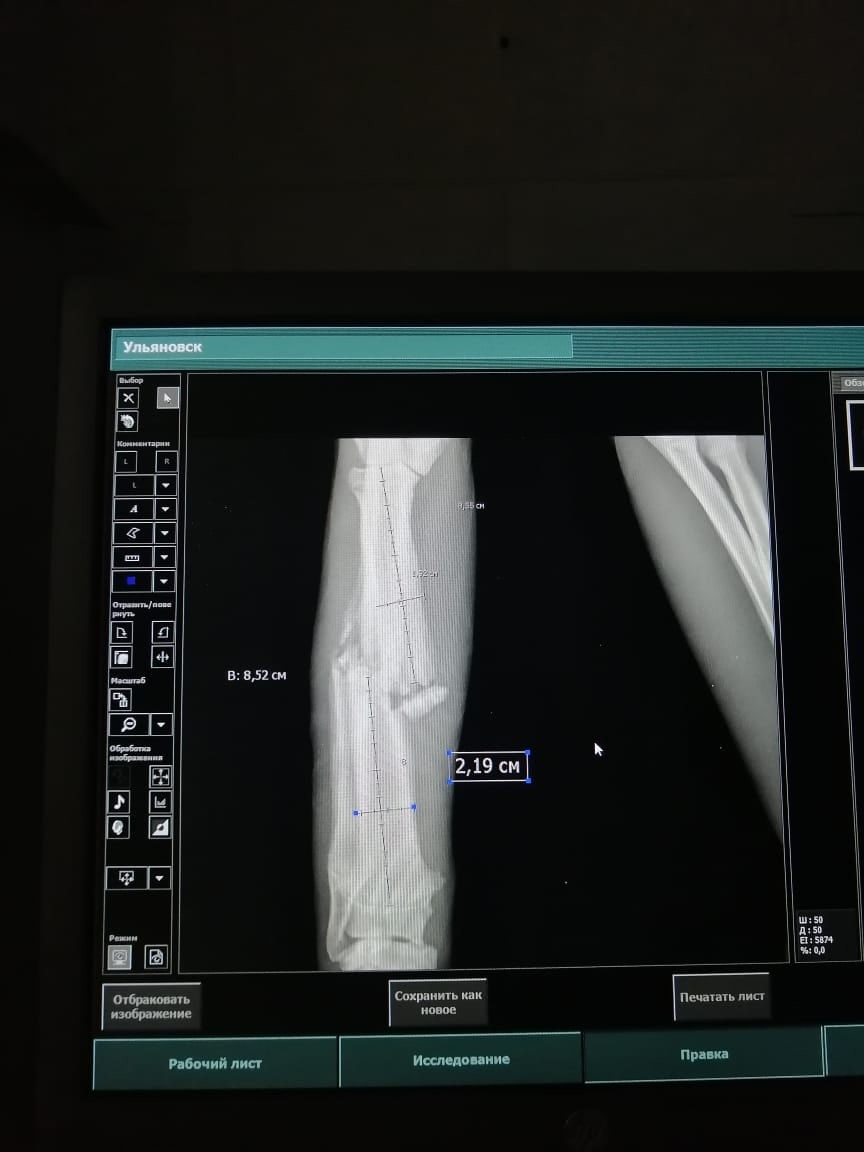

У Давида с переломом лапы нет кураторов, но есть большой шанс на дальнейшую счастливую жизнь.